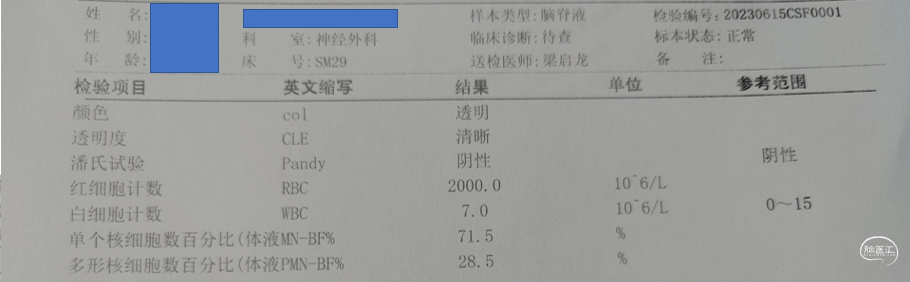

术后化验

2周后停抗生素